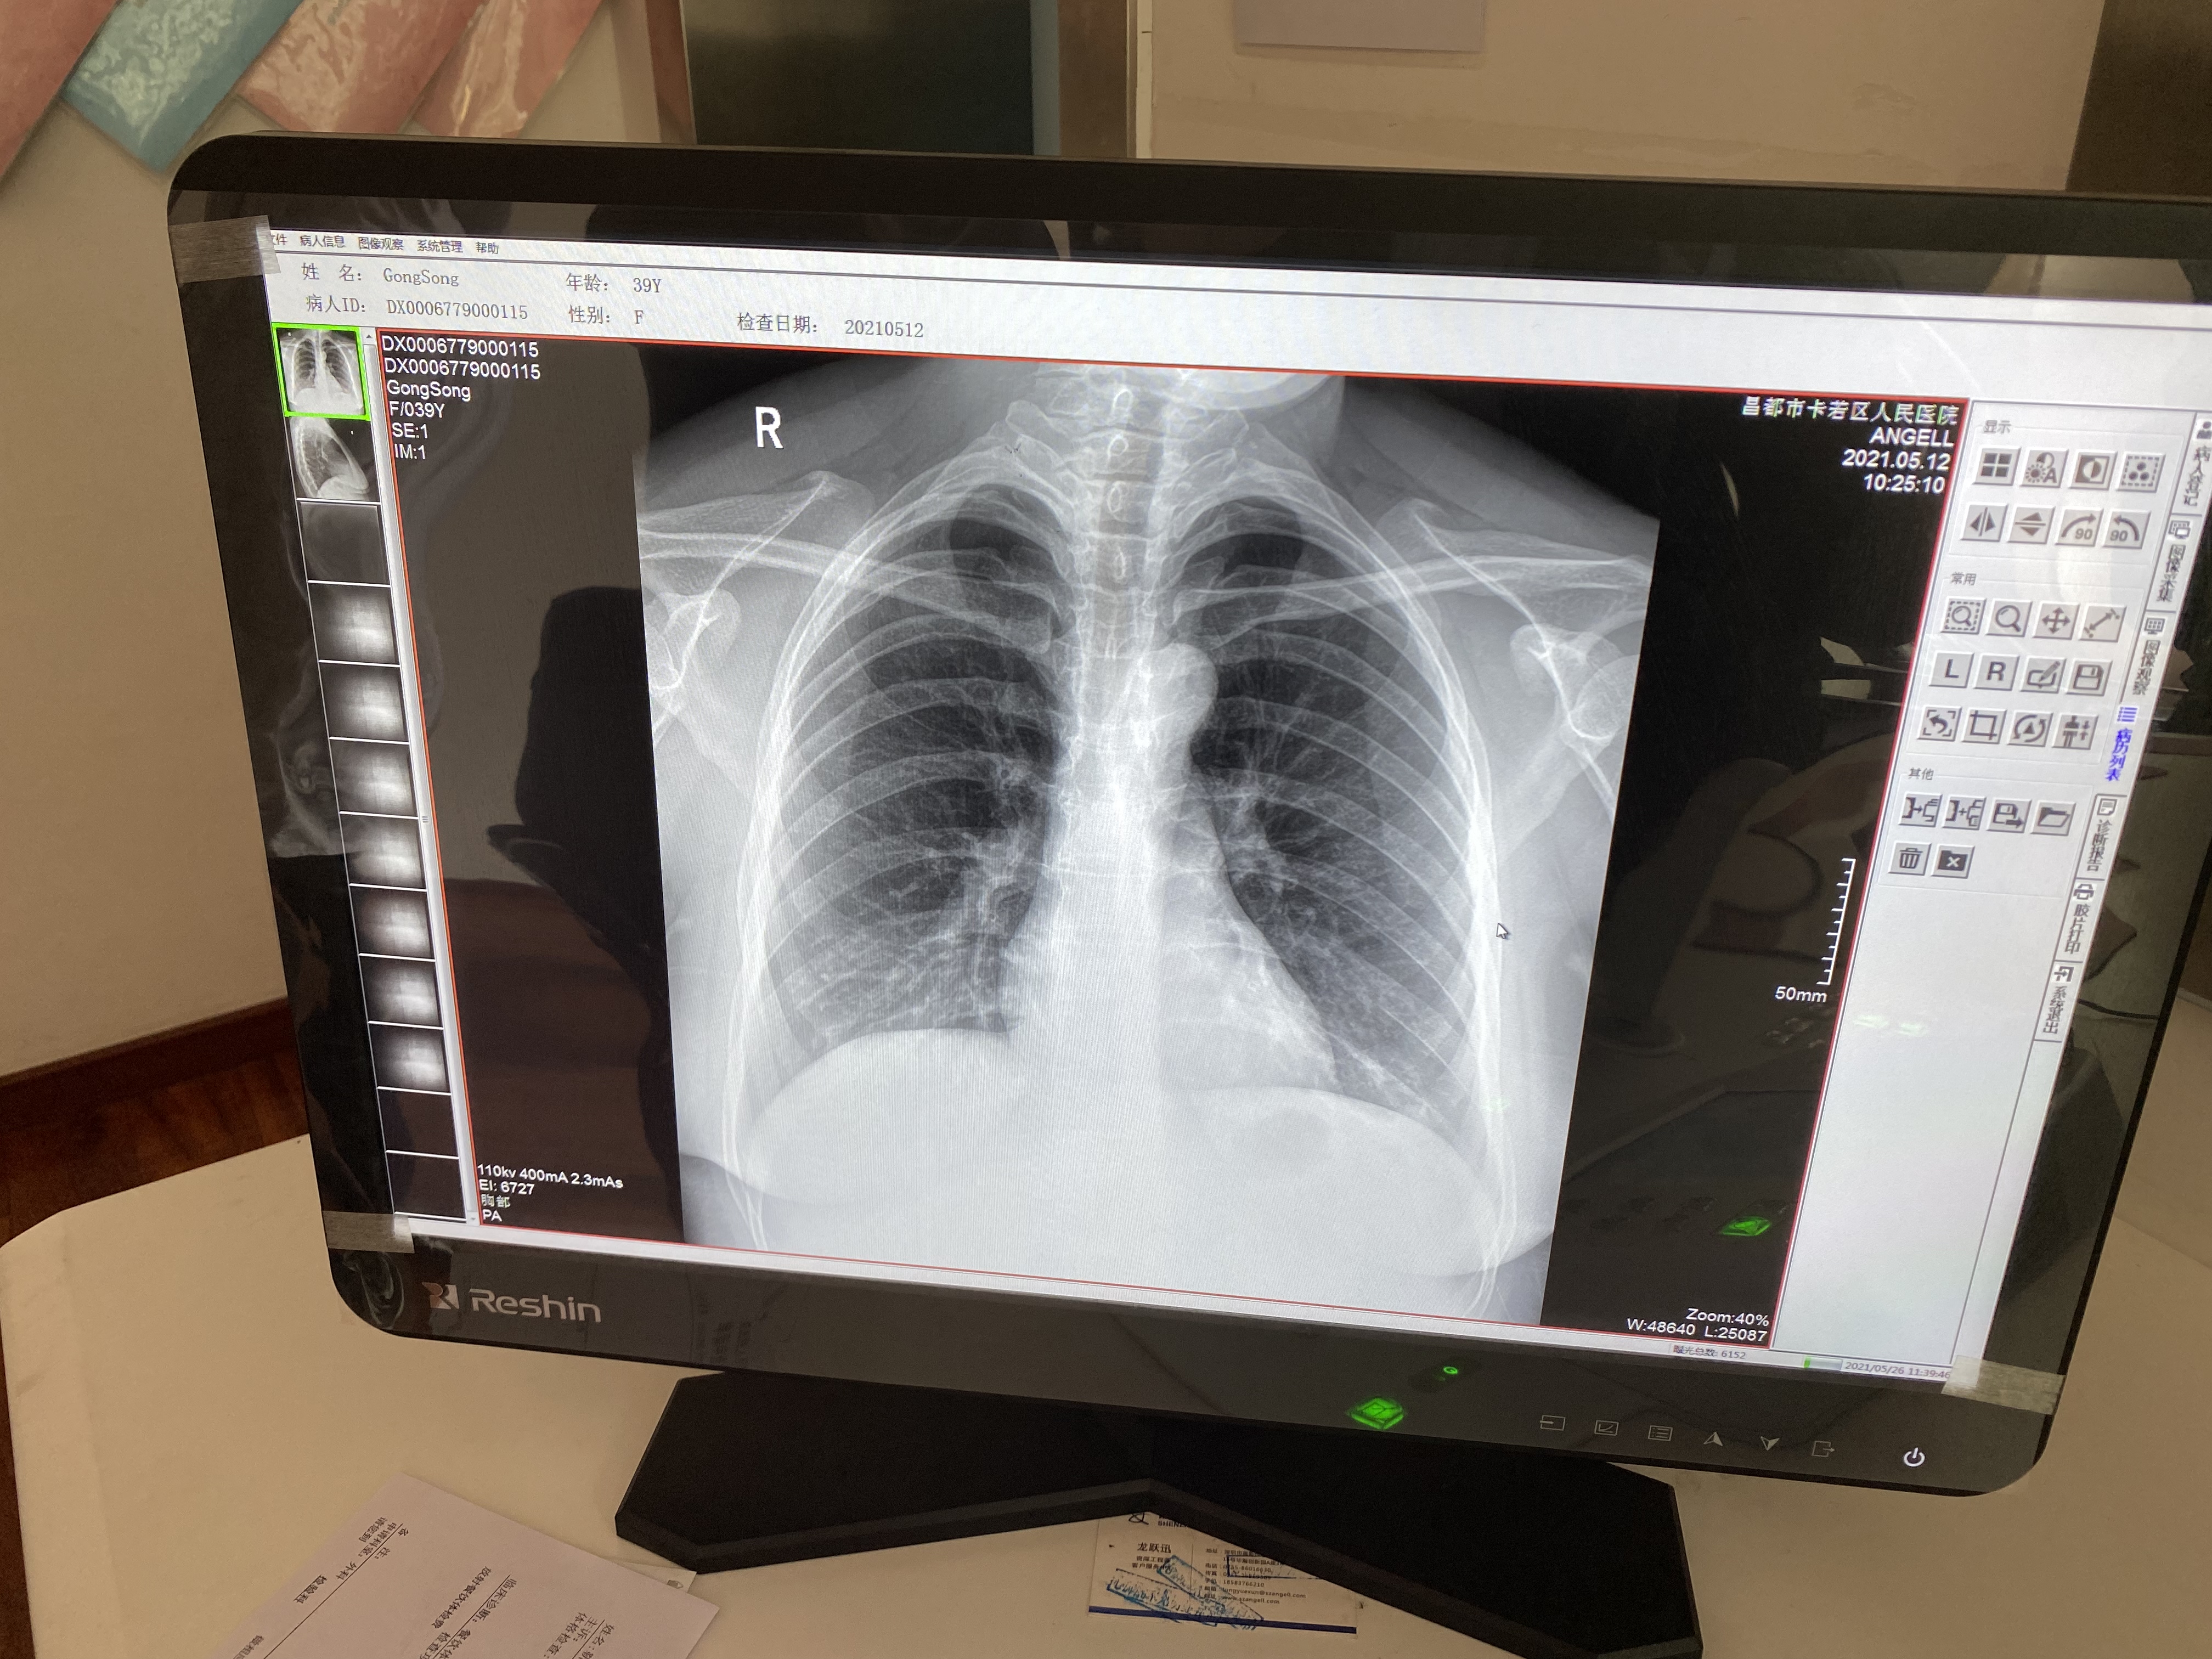

6:腾灵的胸片摄片临床影像

作为一款动态多功能诊断专用DR设备,腾灵支持高清摄片、透视摄影、造影摄影、全脊柱摄影、全下肢摄影检查于一身,满足低人口密度地区的多种数字化X线摄影检查需求。在卡若区人民医院,每天大约有60人左右的检查人次,来自于一区十县 24个镇118乡的藏区百姓,腾灵在过去近一年的服役中赢得了放射科主任及主管技师的一致认可。

“这个设备好得很,现在我们这个医院就1台这个设备,每天都在给病人做检查。摁一下摁扭它就可以立起来,体检病人的时候我们就立起来检查,拍出来的图像很清楚。它也可以横着放,拍腰椎的病人、骨关节的病人,我们摁一下就可以平放摄片。我们现在已经检查了差不多有1多万个病人了,机器没有出现什么问题,工程师也会经常询问设备的情况,这个设备美得很。”操作设备的主管技师说。